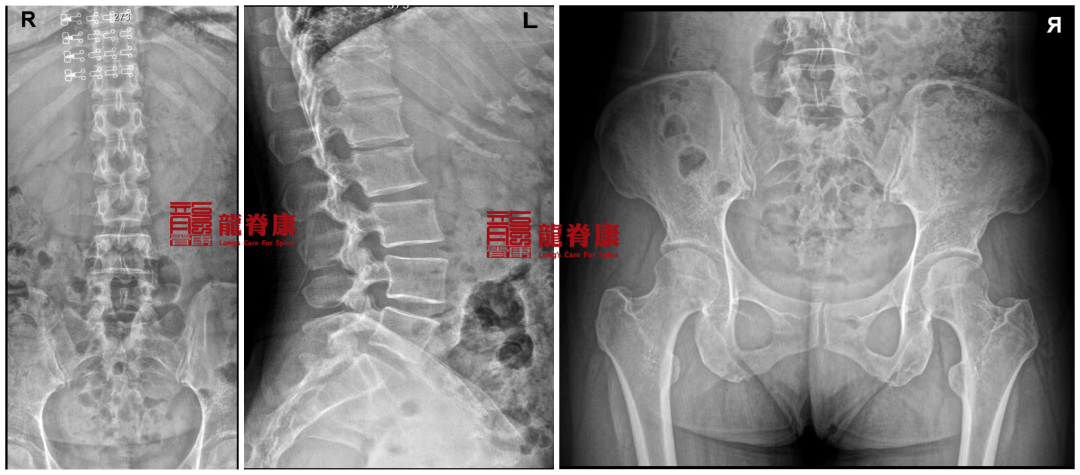

2024-11-7 骨盆腰椎X光提示:骨盆明显左高右低,腰椎L3为中心向左侧凸,棘突偏右。腰椎上段生理曲度反弓。

三、诊断结果

骨盆错位